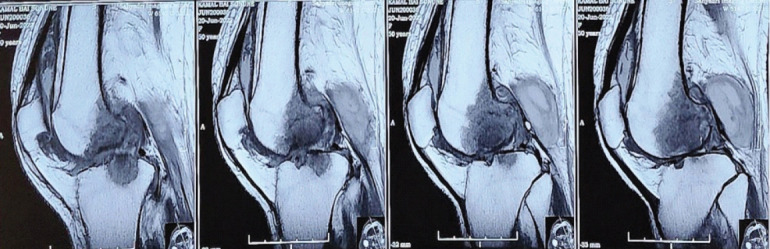

Case report: A 55-year-old female patient of South Asian descent presented with progressive left knee pain and restricted range of motion. Clinical and radiological investigations revealed signs of inflammatory pathology, including elevated serum markers and imaging findings consistent with arthritis. Histopathological examination of the synovial tissue confirmed tubercular arthritis. The patient underwent surgical debridement followed by TKA. Postoperatively, the patient demonstrated significant functional improvement and was closely monitored over a 2-year follow-up period, with no recurrence of infection or prosthesis-related complications.